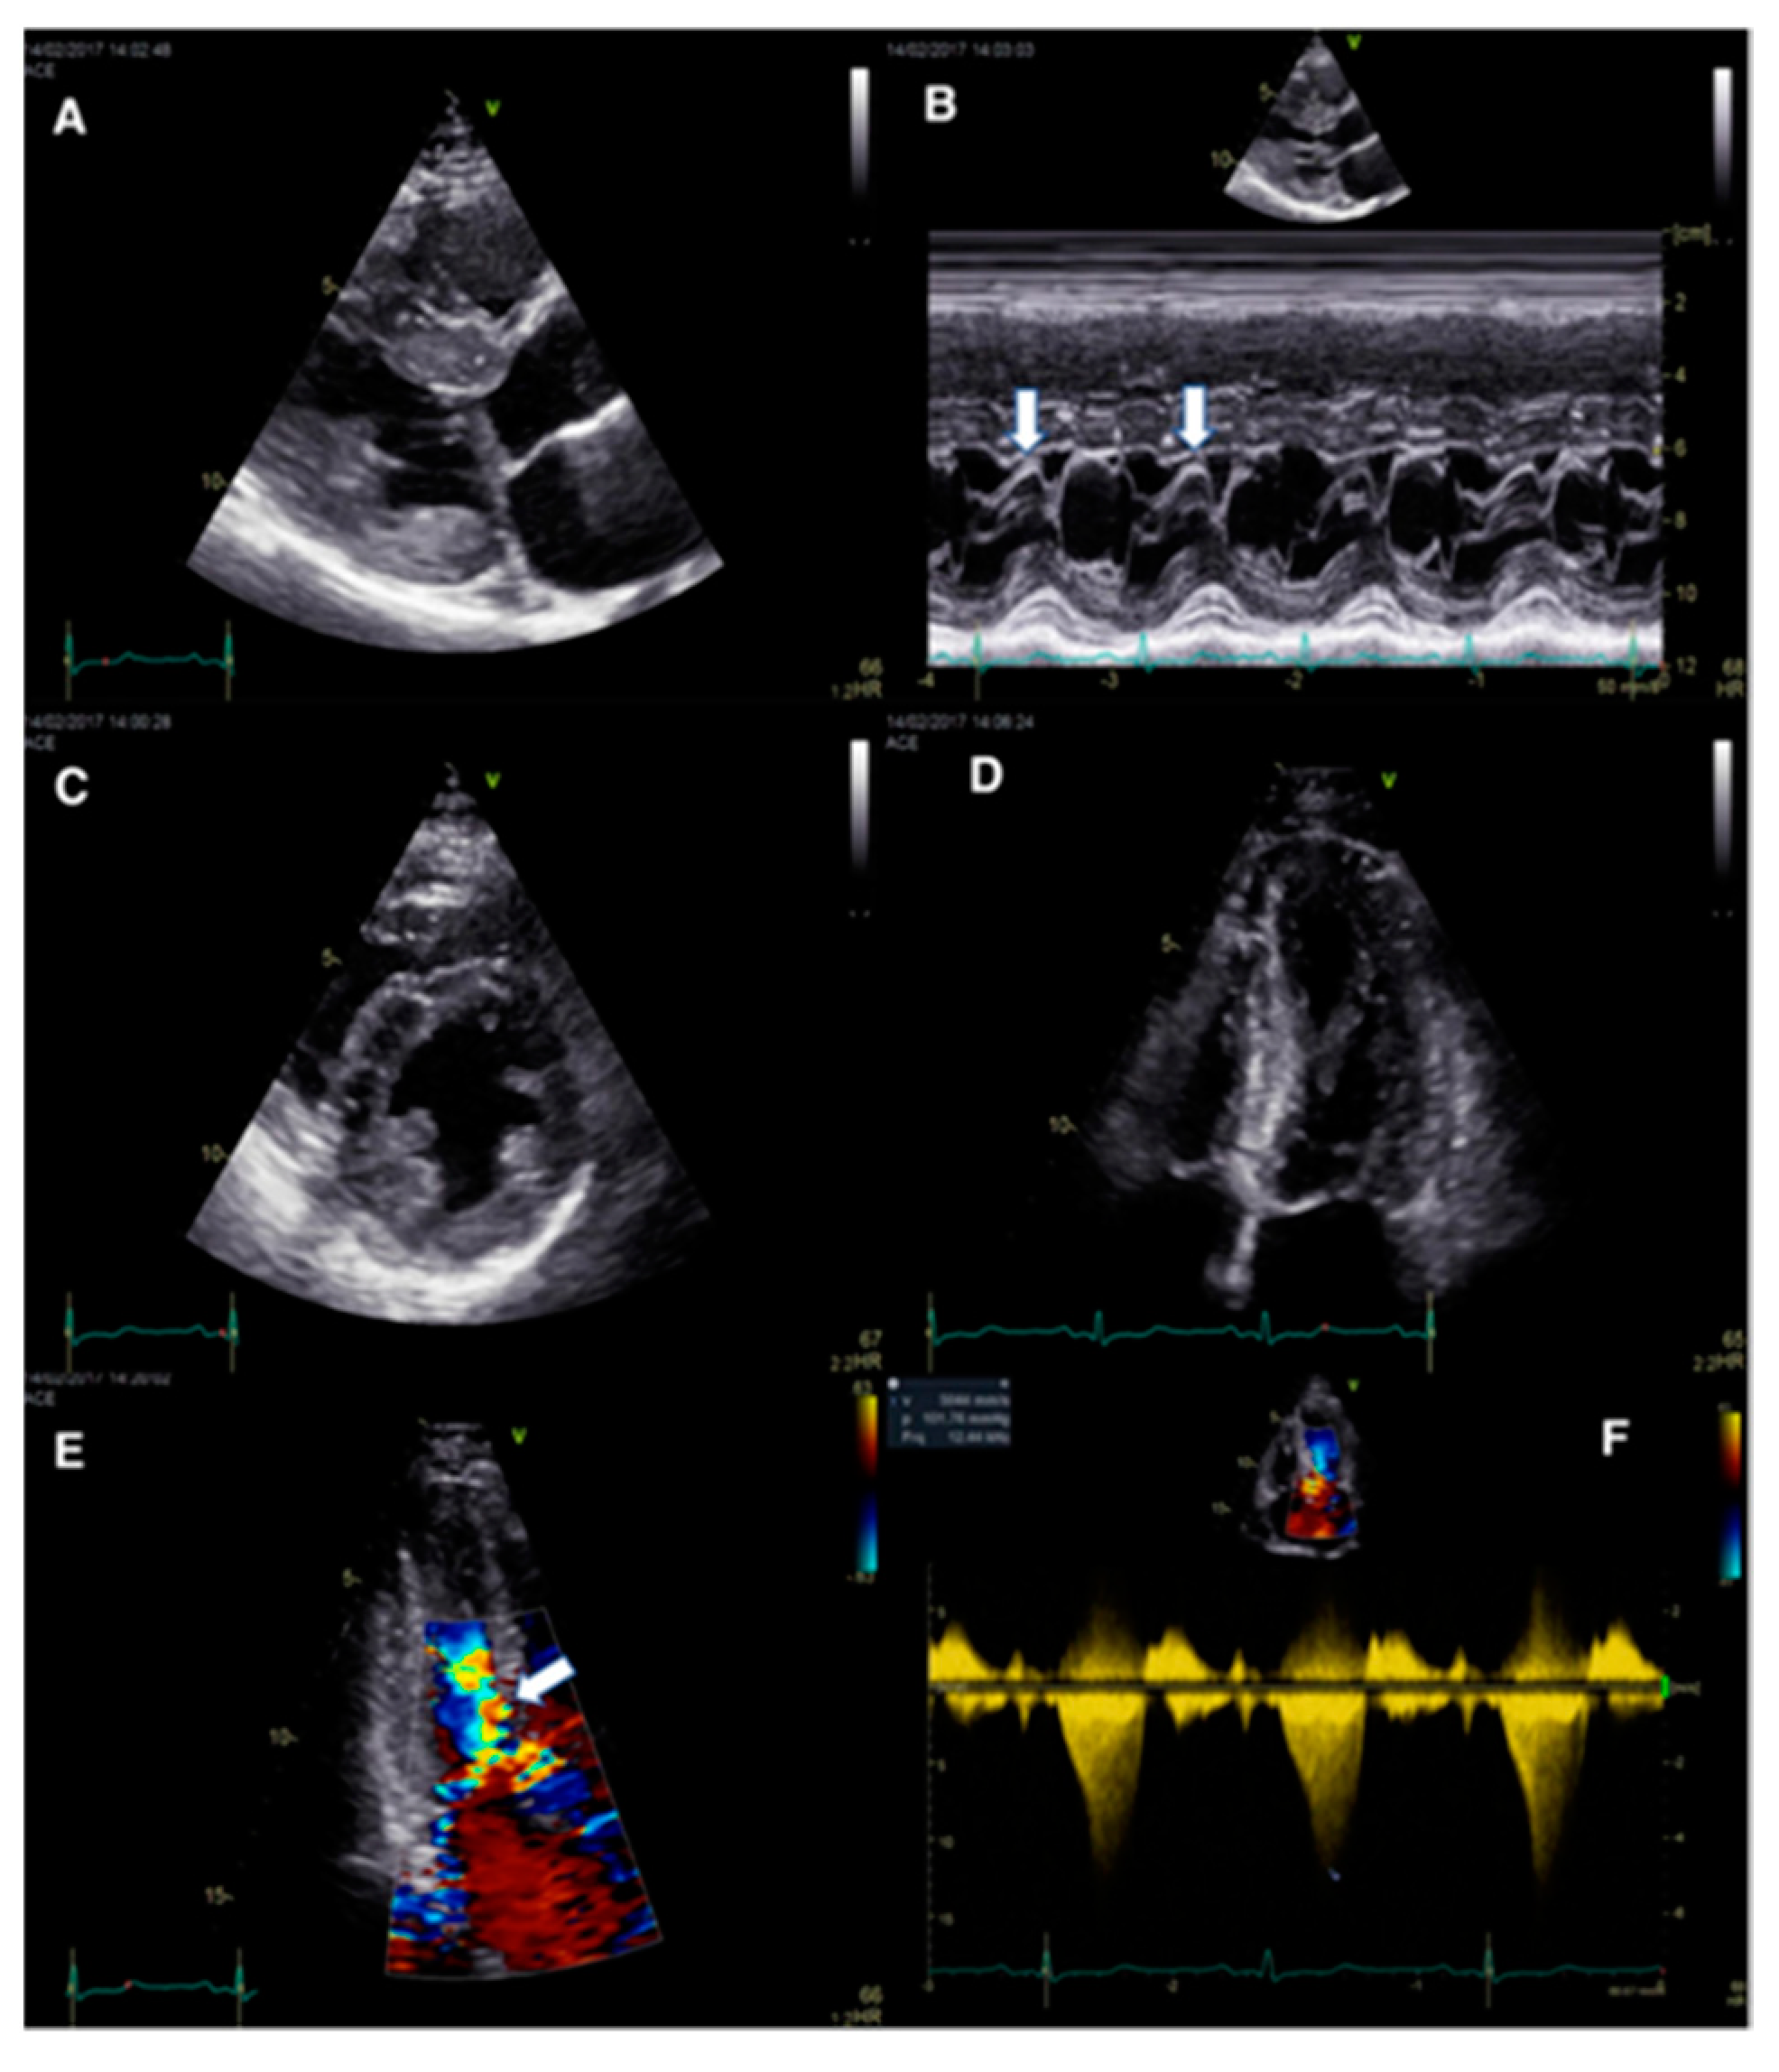

Figure 1.

Complex mechanisms leading to dynamic obstruction in a patient with HCM. Concentric hypertrophy involving mainly the basal septum (diastolic IVS thickness of 15 mm), and elongated mitral leaflets with systolic anterior motion (A); M-mode echocardiography shows the systolic contact of the mitral valve with the IVS (arrows) (B); anterior displacement of the hypertrophied papillary muscles (C,D); moderate eccentric (posteriorly oriented) mitral regurgitation secondary to SAM (E); and significant resting LVOT obstruction by CW Doppler (peak resting gradient of 102 mmHg) (F). Of note, there is severe LVOT obstruction without severe septal hypertrophy, explained by the significant abnormalities of the mitral valve apparatus. HCM hypertrophic cardiomyopathy, IVS interventricular septum, LVOT left ventricular outflow tract. Mandeş L, et al. Journal of Echocardiography 2020; 18: 137–148 [39].